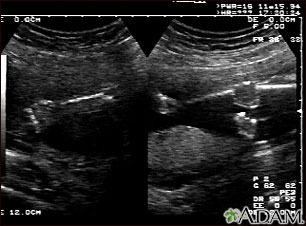

This is a normal fetal ultrasound performed at 19 weeks gestation. This is the type of spilt-screen display you might see during an ultrasound, or if the technician prints a copy of the ultrasound for you. This ultrasound shows both the left arm (seen in the left side of the display), and the lower extremities (seen in the right side of the display). The white areas of the arm or legs is developing bone.